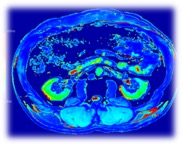

Le CHU de Poitiers a accueilli en novembre 2019 un IRM ultra haut champ à 7 Tesla qui donne accès à une imagerie moléculaire, métabolique, d’une très haute résolution permettant de mesurer la structure et la fonction des organes de façon inégalée. Cette imagerie peut faire espérer des progrès majeurs dans l’étude in vivo, de façon non invasive, de nombreuses pathologies, dans leur prise en charge clinique et le suivi de leur évolution, sous traitement, éventuellement après une chirurgie, en temps réel.

L’équipe DACTIM-MIS au sein du LMA, a pour membres des personnels du CHU et des mathématiciens, spécialisée dans les modèles bio-statistiques et réalistes (systèmes lents-rapides), pour une modélisation du métabolisme du cerveau et du métabolisme tumoral. L’équipe ICONES de XLIM possède quant à elle une expertise reconnue internationalement dans le domaine des images-multivariées, en particulier texturées, par des approches vectorielles et bio-inspirée, et développe des compétences complémentaires pour les algorithmes d’apprentissage automatique, notamment dans le cadre de l’imagerie médicale. Les équipes se connaissent et travaillent ensemble depuis 2012 dans le cadre de la fédération MIRES. C’est donc tout naturellement qu’elles se retrouvent aujourd’hui, avec le CHU, au sein du laboratoire I3M, dont l’objectif est de mettre en oeuvre des techniques innovantes d’Intelligence Artificielle pour le traitement et l’analyse automatique des images multi-modalités, pour l’aide au diagnostic et au suivi thérapeutique dans les pathologies :